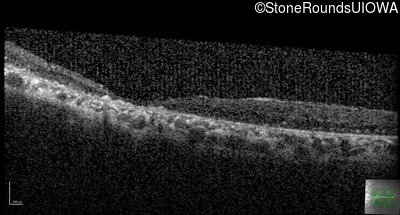

Age at visit: 41 years

This 41 year old man first came to medical attention at age 18 months when exotropia and amblyopia of his right eye were discovered. At age 11 vitreous strands and retinal vascular sheathing were seen. He has had poor night vision and constricted visual fields since his late teens. Later, at age 44 a traction retinal detachment was noted in his left eye and was treated with a scleral buckle.